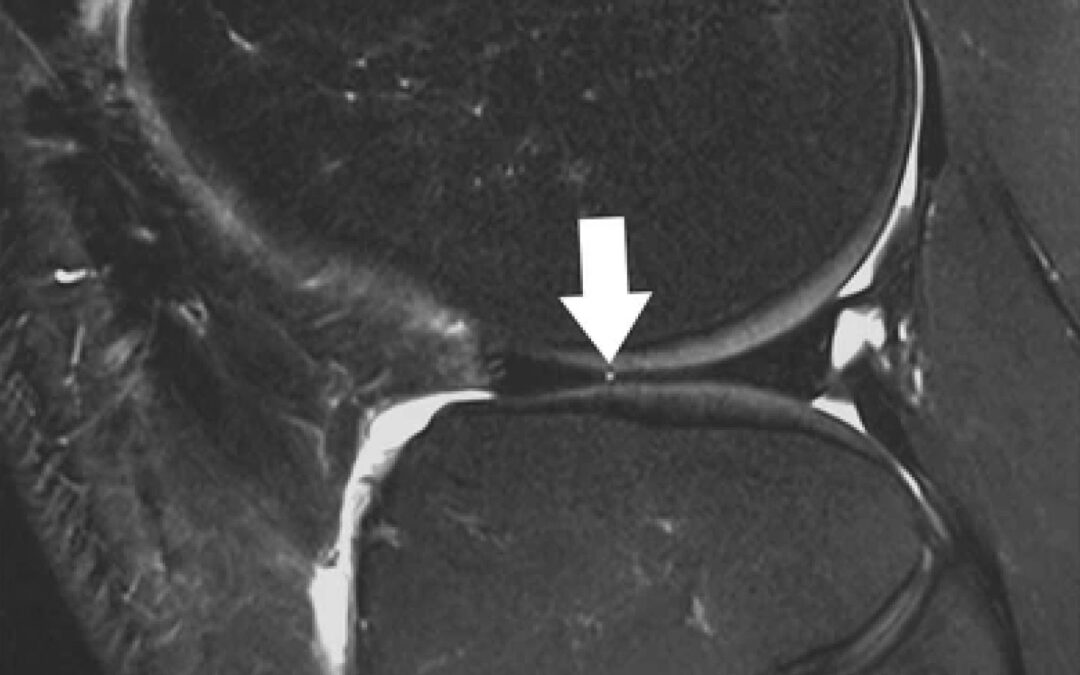

Sagittal T2-weighted, fat-suppressed fast spin echo image of the right knee in a 39-year-old male patient acquired at 3 Tesla (Siemens Healthcare, Erlangen, Germany) using a dedicated 28 channel transmit-receive knee coil shows a small radial tear of the lateral meniscus (arrow). Reprinted from Bolog NV, Andreisek G. Reporting knee meniscal tears: technical aspects, typical pitfalls and how to avoid them. Insights Imaging 2016;7:385–398. https://doi.org/10.1007/s13244-016-0472-y. Use is per Creative Commons Attribution 4.0 International License.